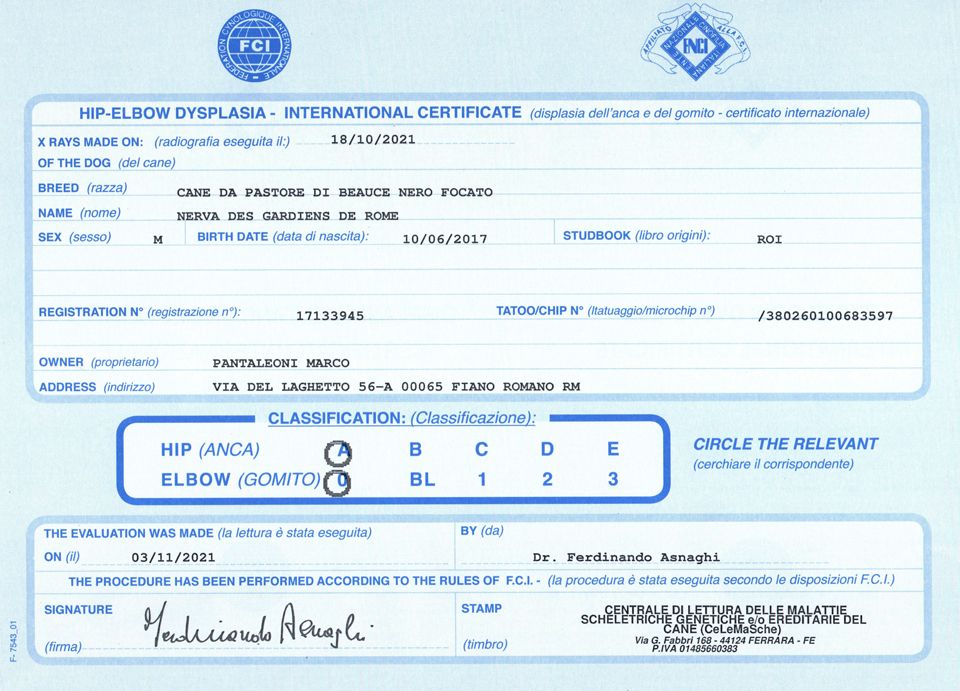

Nerva Des Gardiens De Rome

mâle

Berger de Beauce

né le

10/06/2017

NERVA des Gardiens de Rome

| Sexe | Mâle |

| Couleur | Noir et Feu |

| Tatouage | 380260100683597 |

| Inscrit au LOF ? | Italie |

| N° origine | LO17133945 |